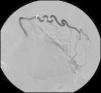

Para confirmar que a malformação vascular detetada era exclusivamente de natureza arterial foi efetuada angiografia seletiva da 4a à 7a artérias intercostais esquerdas que, além de revelar aumento do calibre das artérias intercostais (figs. 9 e 10), demonstrou fístula exclusivamente arterial entre os ramos da circulação sistémica acima referidos e o ramo esquerdo da artéria pulmonar através de novelo arterial (figs. 10 e 11). As artérias brônquicas, nomeadamente as do mesmo lado da malformação descrita, não foram avaliadas angiograficamente.